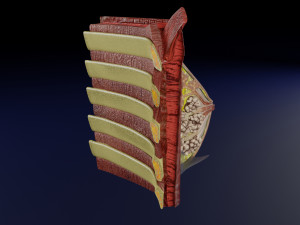

This is a 1:1 scaled model of right breast cut opened in sagittal plane to reveal its internal antomy and histology (schematic). The deeper parts and fascial layers are also depicted to give a very detailed approach to the model. The full layers starting from skin, nipple areola, till intercodtal muscles and ribs are also depicted.